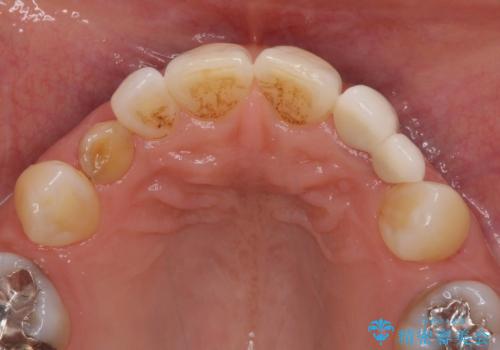

上顎は左右ともに小臼歯が欠損しており、右側は乳前歯が残っている状態でした。

ブリッジによる補綴治療にて、欠損や隙間を補完することとしましたが、神経を取り除いたり、審美的に不自然になることを避けるため、部分矯正を併用することとしました。

乳歯は事前に抜歯することとしました。